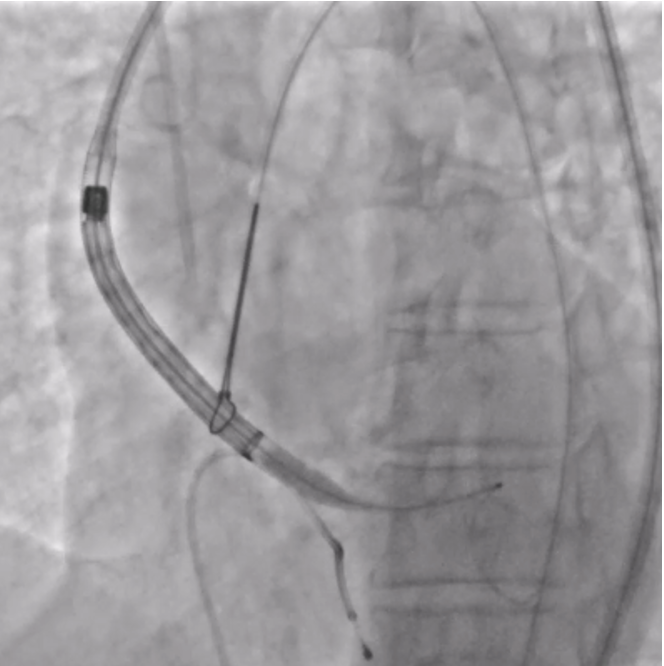

The patient was planned for transfemoral TAVI. Both left and right femoral arteries were punctured under ultrasound guidance. A temporary pacemaker (TPA) was placed in the right ventricle via the left femoral artery, and the right femoral artery sheath was upgraded to the 14Fr sheath. Selective left coronary angiography revealed normal coronaries. Through the right femoral artery, a snare was deployed in the abdominal aorta. The native bicuspid aortic valve was crossed with an Lunderquist wire, which was advanced into the left ventricle. Using pigtain, angiographic gradient was measured, showing severe aortic stenosis. Predilatation was performed using a 20 mm Z-MED balloon with satisfactory results. The TAVI valve, a self-expanding valve, was advanced across the native valve with the aid of the snare and positioned accurately in the cusp-overlap view. Under rapid pacing, the valve was deployed up to 80%, and after confirming satisfactory depth, full deployment was completed in the coplanar view. Final angiographic assessment showed no paravalvular leak (PVL) or aortic regurgitation (AR), with valve depth of 4–5 mm at the NCC and 6–7 mm at the LCC. Femoral closure was performed successfully without vascular complications.